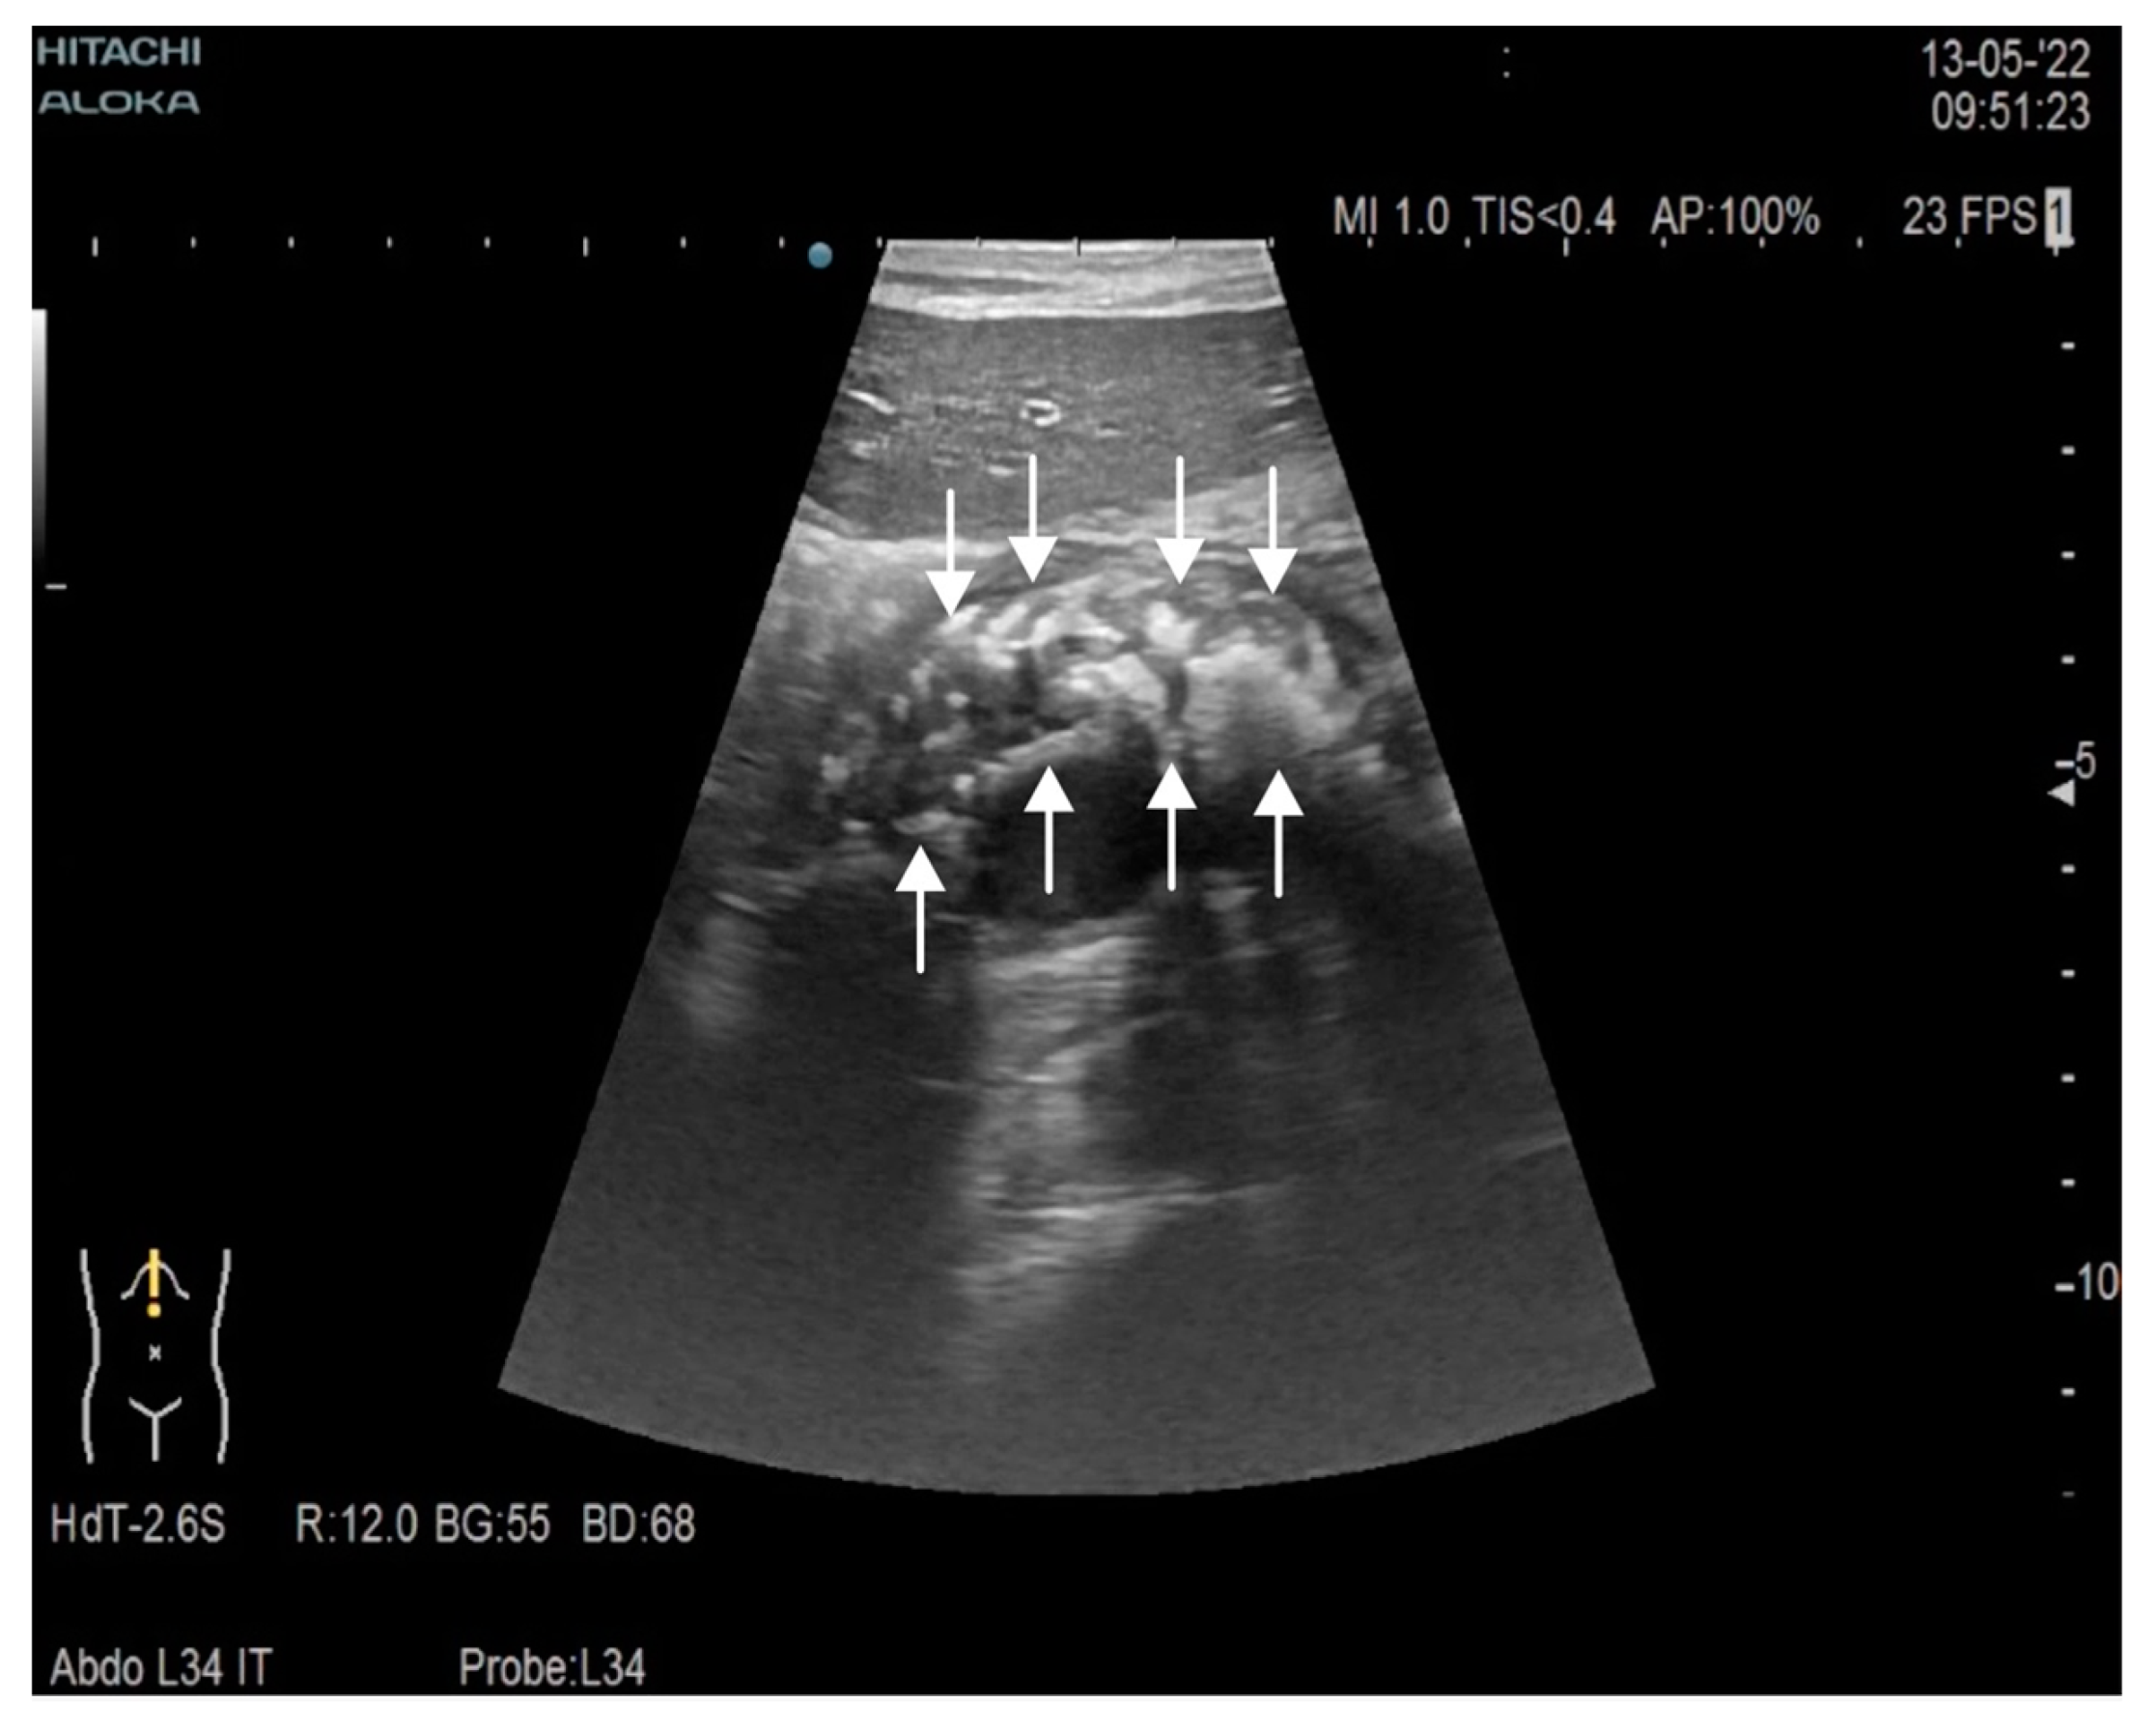

2. Case Report